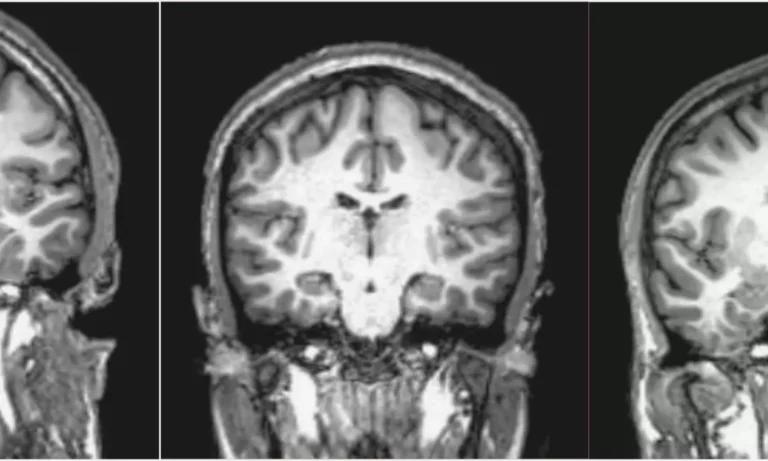

In some cases, imaging tests, such as MRI or CT scans, may be ordered to rule out any underlying physical conditions that could be causing the psychotic symptoms. Additionally, the clinician may consult the Diagnostic and Statistical Manual of Mental Disorders (DSM-5) to ensure the diagnosis aligns with the established criteria for specific psychotic disorders.